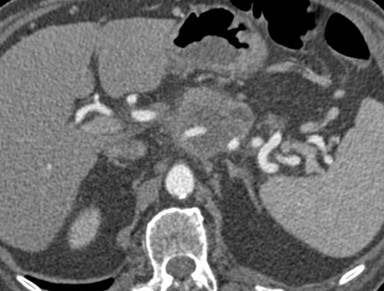

After removal of all needles, a CT scan with iv contrast medium administration was performed to evaluate the absence of vascular complications given the relative proximity of the celiac trunk; it revealed a vasoconstriction of splenic artery associated with the presence of multiple small spleen defects of perfusion (Figure 2ab), that were not present at CT scan performed before treatment (Figure 3). The day after the procedure the patient underwent a contrast enhanced ultrasound (CEUS) that did not revealed ischemic areas in the splenic parenchyma and showed normal patency of splenic artery (Figure 4). During the hospital stay, complete blood counts and electrolyte levels were monitored and liver function tests were performed twice a week.

Figure 2. CT scan showed vasoconstriction of splenic artery (a. white arrow) associated with the presence of multiple small spleen defects of perfusion (a., b.). |